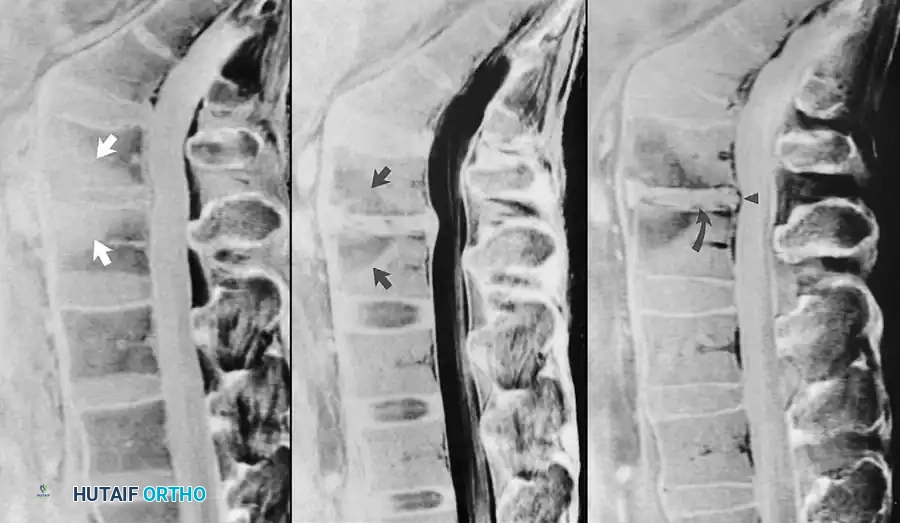

Fig. 2-27 Postoperative discitis. A, Sagittal T1-weighted image exhibits reduced marrow signal adjacent to narrowed L4-5 intervertebral disc (arrows). B, Sagittal T2-weighted image reveals corresponding hyperintense areas of vertebral marrow edema (arrows). C, After administration of gadolinium, sagittal T1-weighted image exhibits enhancement of vertebral marrow, intervertebral disc (curved arrow), and posterior longitudinal ligament (arrowhead).

Gadolinium contrast is also indispensable in the postoperative evaluation of the spine for discitis. While reactive changes in the disc space and adjacent vertebral end plates (Modic changes) are frequently seen after uncomplicated spinal surgery, the classic MRI triad for postoperative discitis includes:

1. Vertebral body end plate enhancement.

2. Disc space enhancement.

3. Enhancement of the posterior longitudinal ligament.